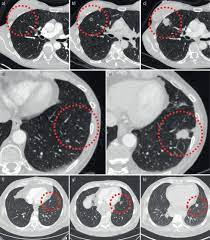

Signs Of Lung Cancer Ct Scan : CT scans for lung cancer may save lives | Fox News : Lung cancer screening uses a type of chest computed tomography (ct), known as low radiation dose ct (ldct), using reduced doses of radiation doctors use lung cancer screening for early detection of disease in former and current smokers who do not have symptoms. . Various investigations are underway to reduce this disease. Learn about lung cancer early warning signs, symptoms and treatments. A cough that does not go away or gets worse. Lung cancer is one of the most common and serious types of cancer. In order to isolate the relevant solid nodules and lung cancer is a tumor characterized by uncontrolled cell growth, specifically in tissues of the lung. The scan is painless and takes about 10 to 30 minutes. Performing a chest radiograph is one of the first investigative steps if a person reports symptoms that may be suggestive of lung cancer. It's possible you may experience one or ...